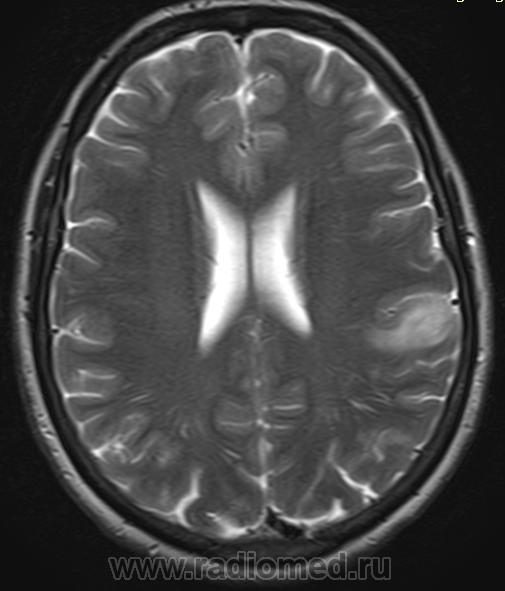

Fazekas grades. Мультифокальная лейкоэнцефалопатия. Резидуальная энцефалопатия на мрт. Прогрессирующая мультифокальная лейкоэнцефалопатия кт. Гипертензионная энцефалопатия на мрт.

Fazekas grades. Мультифокальная лейкоэнцефалопатия. Резидуальная энцефалопатия на мрт. Прогрессирующая мультифокальная лейкоэнцефалопатия кт. Гипертензионная энцефалопатия на мрт.

Fazekas grades. Brain MRI. Wilson Brain MRI. Фазекас классификация мрт. Лейкоареоз Фазекас.

Fazekas grades. Brain MRI. Wilson Brain MRI. Фазекас классификация мрт. Лейкоареоз Фазекас.

Fazekas grades. Фазекас классификация мрт. Очаги Фазекас мрт. Шкала Фазекас мрт. Церебральная микроангиопатия головного мозга Fazekas 2 степени.

Fazekas grades. Фазекас классификация мрт. Очаги Фазекас мрт. Шкала Фазекас мрт. Церебральная микроангиопатия головного мозга Fazekas 2 степени.